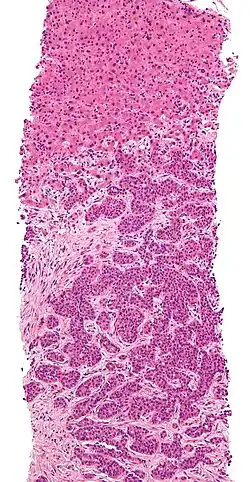

Bei der derzeit am häufigsten durchgeführten sonografisch gesteuerten Leberbiopsie wird der Patient zunächst mittels Ultraschall untersucht und der Punktionsort festgelegt. Es erfolgt eine ausführliche Hautdesinfektion. Dann erhält der Patient eine Sedierung (z. B. mit Midazolam) und eine örtliche Betäubung im Bereich der Punktionsstelle. Daraufhin wird die Punktionskanüle vorbereitet und der Stanzzylinder entnommen. Der Stanzzylinder wird in eine Konservierungslösung eingebracht und zum Pathologen geschickt. Dort wird das Gewebe in Paraffin eingebettet, in Dünnschnitte zerteilt, gefärbt und mittels Mikroskop untersucht. Der erhobene Befund geht an den Untersucher zurück (meist innerhalb von 1–2 Tagen).